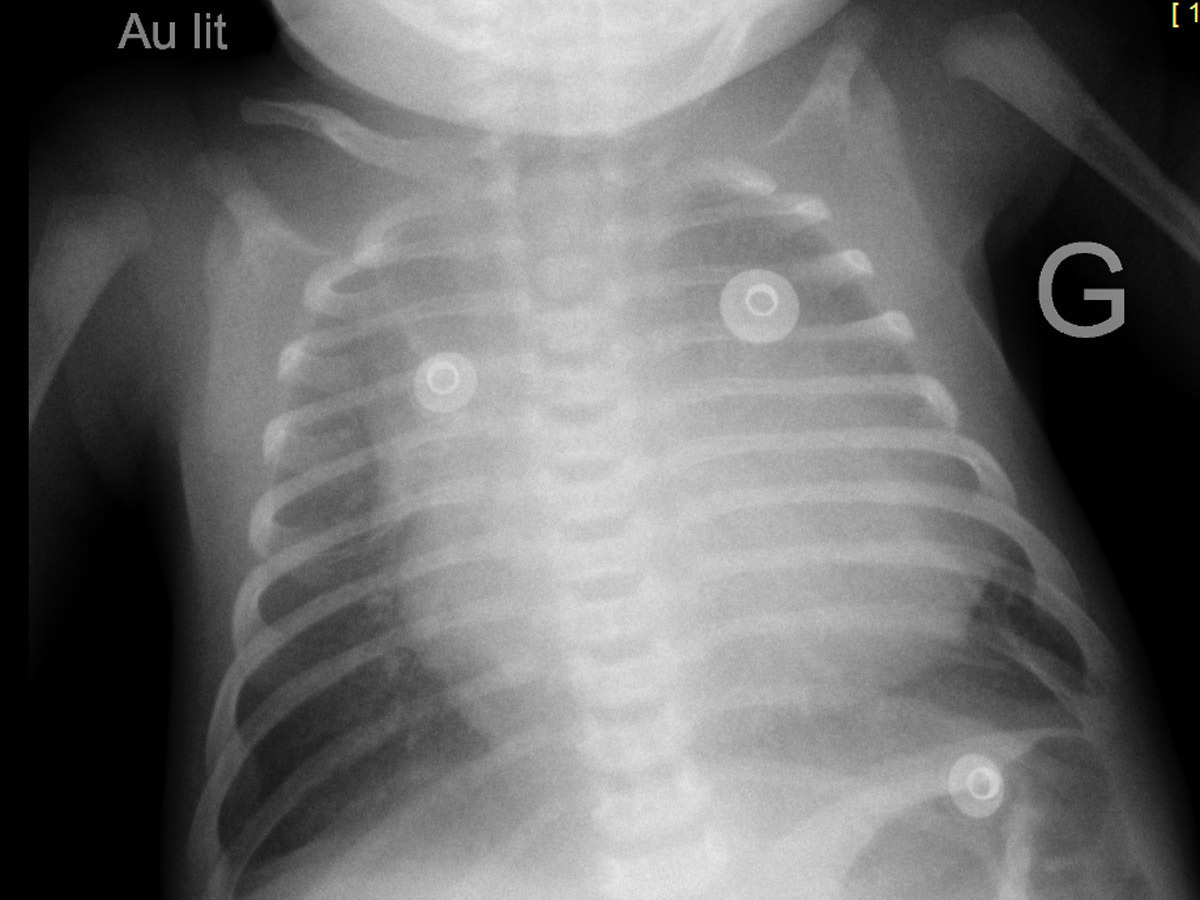

À l’examen clinique ce jour, vous notez : poids 2 800 g, taille 46 cm, PC 35 cm. Fréquence cardiaque 145/mn, fréquence respiratoire 25/mn. Enfant rose, temps de recoloration cutanée 1 seconde, pas de marbrures, extrémités chaudes. Bruits du cœur réguliers, pas de souffle cardiaque audible, pouls fémoraux et huméraux perçus. Murmure vésiculaire bilatéral et symétrique, pas de bruit surajouté. Enfant eupnéique. Abdomen souple, pas d’hépatomégalie. Bon tonus axial et périphérique. Fontanelle normotendue. Reste de l’examen sans particularité.